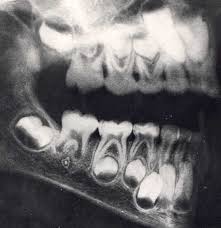

X Ray Of Human Jaw With Teeth Dental Visit X Ray Human Dental